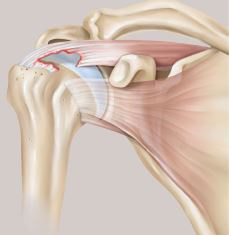

In der arthroskopischen Operationstechnik wird ein sehr dünnes Stahlrohr (6 mm Durchmesser) durch einen kleinen Hautschnitt in das Schultergelenk eingeführt. In diesem Stahlrohr liegt eine stabförmige Kamera (4 mm Durchmesser). Durch weitere kleine Hautschnitte werden die arthroskopischen Instrumente in das Gelenk eingeführt. Mit diesen Instrumenten kann der Operateur die abgerissenen Sehnen fassen und bewegen und jede noch so kleine Bewegung über das Kamera-Bild am Monitor verfolgen. Es werden dann nicht-auflösbare Fäden mittels speziellen Ankern im Knochen fixiert und über diese Fäden werden die gerissenen Sehnen wieder an den Knochen befestigt (vgl. Abb. 2).